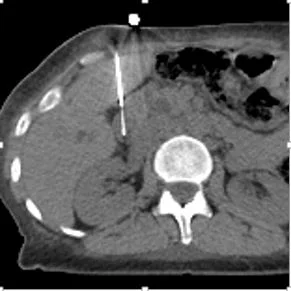

Transhepatic biopsy! Gastric bypass precludes endoscopic approach.